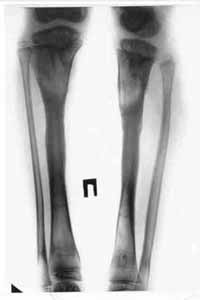

| Results of treatment. | |

| Results of treatment. |